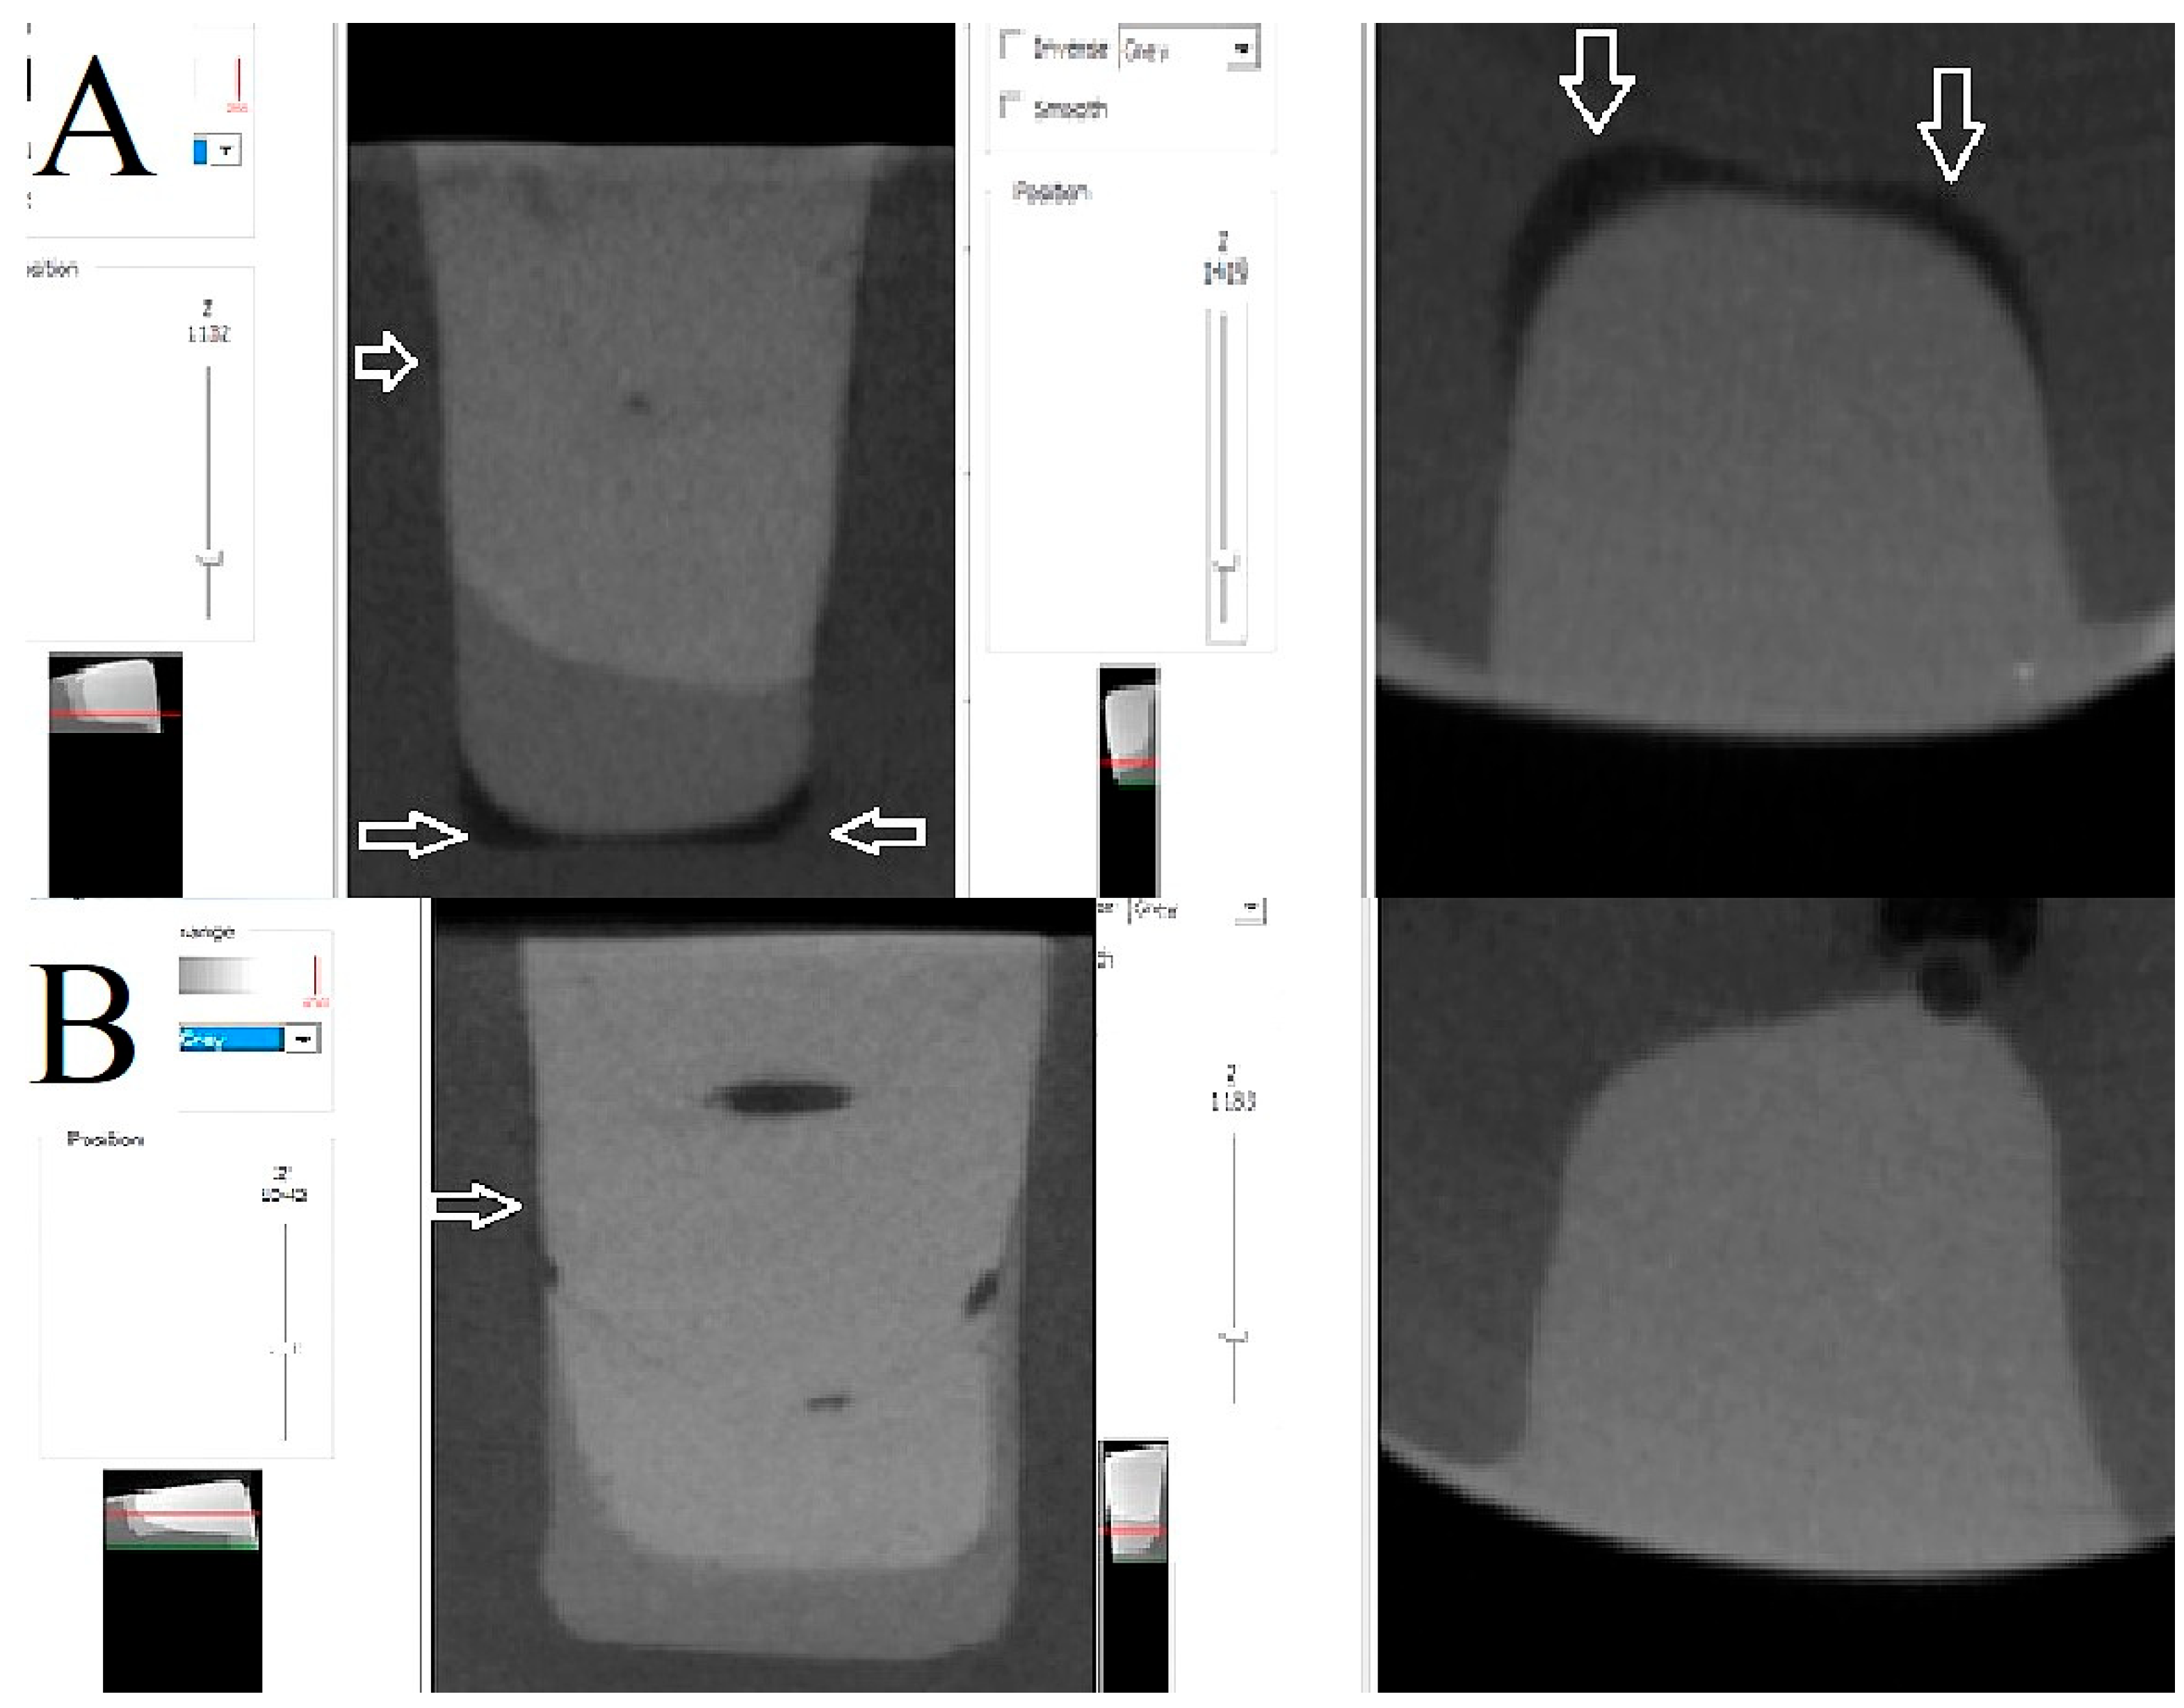

2.2. Micro-Computed Tomography Measurement—3D Internal Adaptation and Porosity

3.1. Micro-Computed Tomography Measurement—3D Internal Adaptation

3.2. Micro-Computed Tomography Measurement—3D Closed Porosity